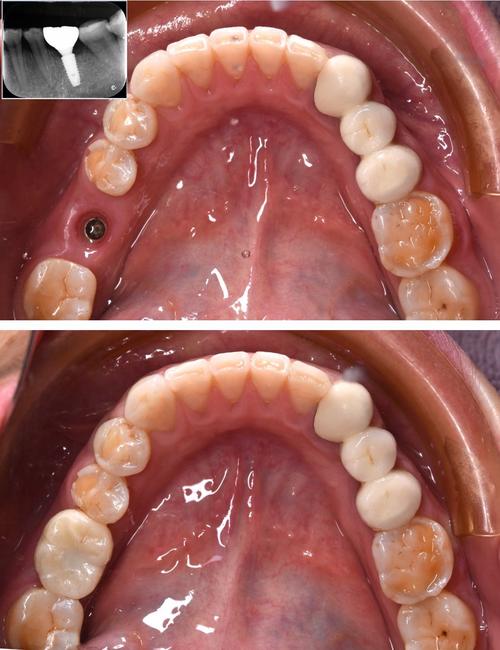

医生资质与经验:种植牙的“灵魂”

种植牙是“外科手术+修复工艺”结合的技术,医生的能力比品牌更重要,优先选择:① 具有口腔外科或种植专业背景的医生(硕士以上学历优先);② 临床经验丰富(完成种植案例超1000例,尤其擅长类似自身情况的病例);③ 能熟练掌握数字化技术(如导板设计、导航种植),可通过查看机构官网、卫健委官网(查询医生执业信息)或要求查看医生案例来判断。

设备与技术:精准度的保障

先进的设备能降低手术风险,提升成功率,核心设备包括:① CBCT(三维口腔CT):可精准测量骨量、神经血管位置,避免损伤;② 口内扫描仪:替代传统取模,提高舒适度和模型精度;③ 种植机:具备扭矩控制功能,确保种植体植入力度合适,若需要即刻种植、全口种植等技术,需确认机构是否具备相应的技术储备。